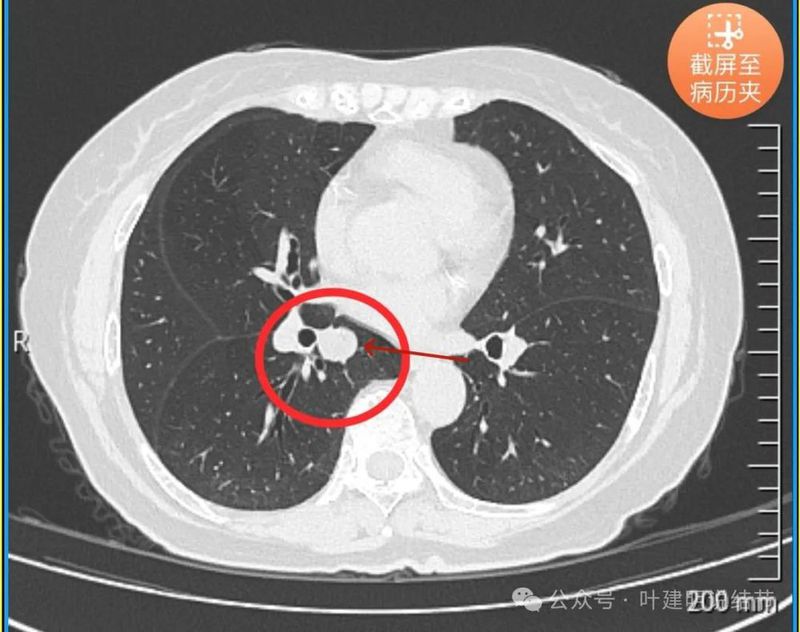

病灶边缘光滑,有血管穿出来似的。

表面光滑,有膨胀性。

内部密度较为均匀,就位于肺门部。

边缘光滑,实性,有膨胀感。

与血管关系近。

边缘区域与下肺静脉间隙不太清楚。